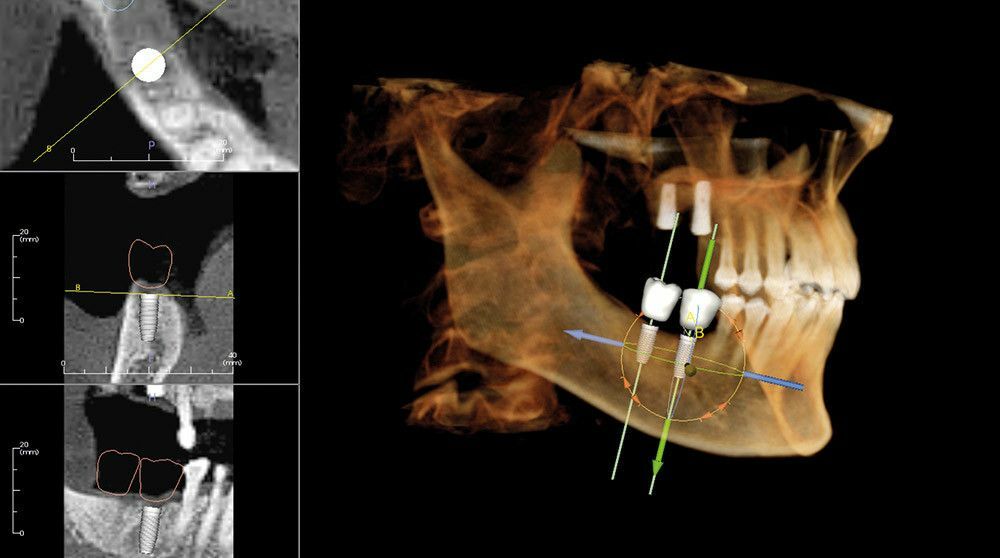

Имплантология: высокоточные планы имплантации